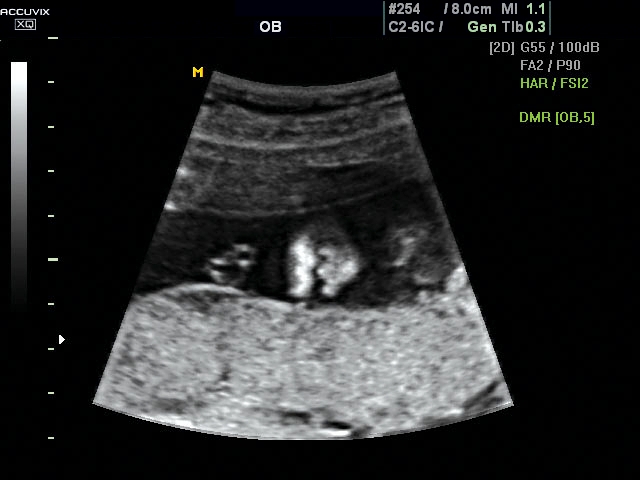

Magzati koponya képe normál 2D módbanMagzati koponya 2D képe bekapcsolt Dynamic MR funkcióvalMagzat törzsének képe normál 2D módbanMagzat törzsének képe bekapcsolt Dynamic MR funkcióvalMagzat felsőajakjának és orrának képeMagzat felsőajakjának és orrának képe bekapcsolt Dynamic MR funkcióval

A pontos analízis és diagnózis iránti egyre növekvő igény kiszolgálására a MEDISON egy új real time képfeldolgozó technológiát fejlesztett ki Dynamic MR™ elnevezéssel. Az eljárás a diagnosztikus ismeretanyagot a precizitás és a pontosság egy teljesen új szintjére emeli. Használata az alapvető 2D ultrahang képinformáció real time, kivételesen kristálytiszta és kiemelkedően részletezett megjelenítését teszi lehetővé tűéles kontúrok és finoman rajzolt szövetstruktúra mellett. A DMR™  technológia ideális eszköze az ultrahang-diagnosztikának kezdve a szülészet-nőgyógyászattól a foetalis echon át az általános alkalmazásokig.